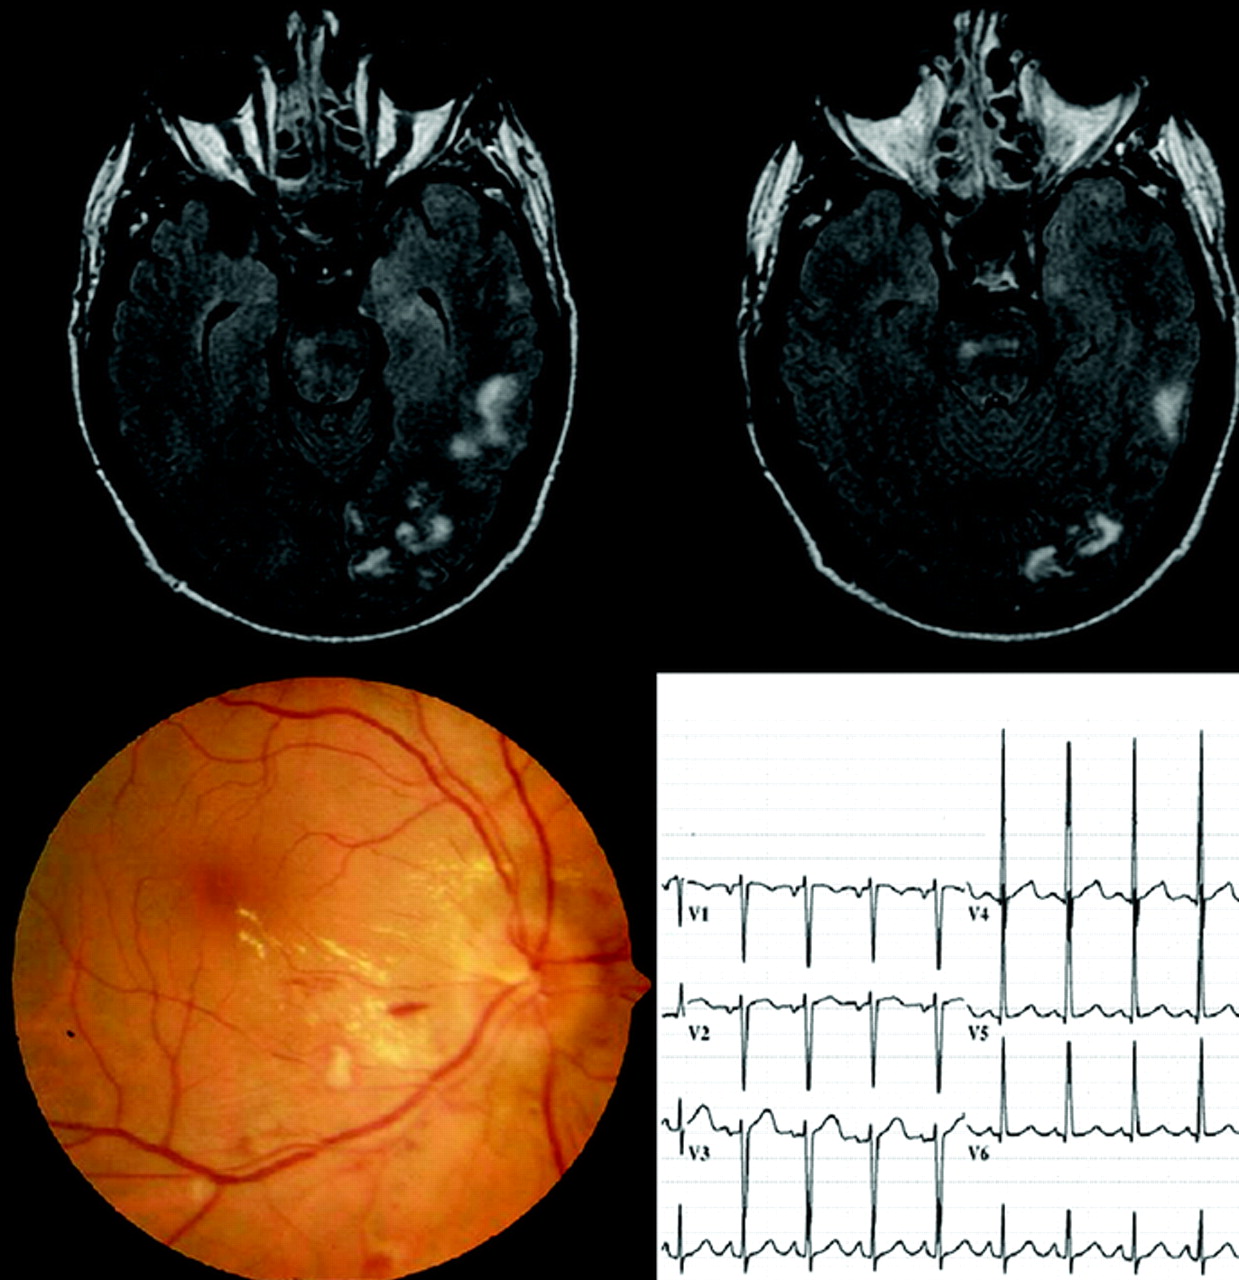

52岁的男人十分发达谵妄和癫痫发作与高血压有关。MRI显示左半球和脑干病变(图)。深刻的风潮杜绝可视化的手艺人,然而急性高血压性视网膜病变瞳孔扩张(见后变得明显图)。心电图(图)和超声心动图显示左心室肥大。抗高血压治疗,大多数病变2周内解决。

图。天赋MRI大脑左半球显示单边和双边桥的病变。这些病变缺席在扩散加权图像(图中未显示)和符合细胞毒性水肿。眼底出血和棉花斑点与恶性高血压一致。2心电图显示左心室肥大。

高血压脑病通常导致对称,后主要的皮层和皮层下病变。额颞叶、放射冠、桥的,小脑病变或严格单方面病变发生一般较少。1在任何原因不明的MRI异常和高血压患者,注意应该指向其他器官损伤特别是视网膜。